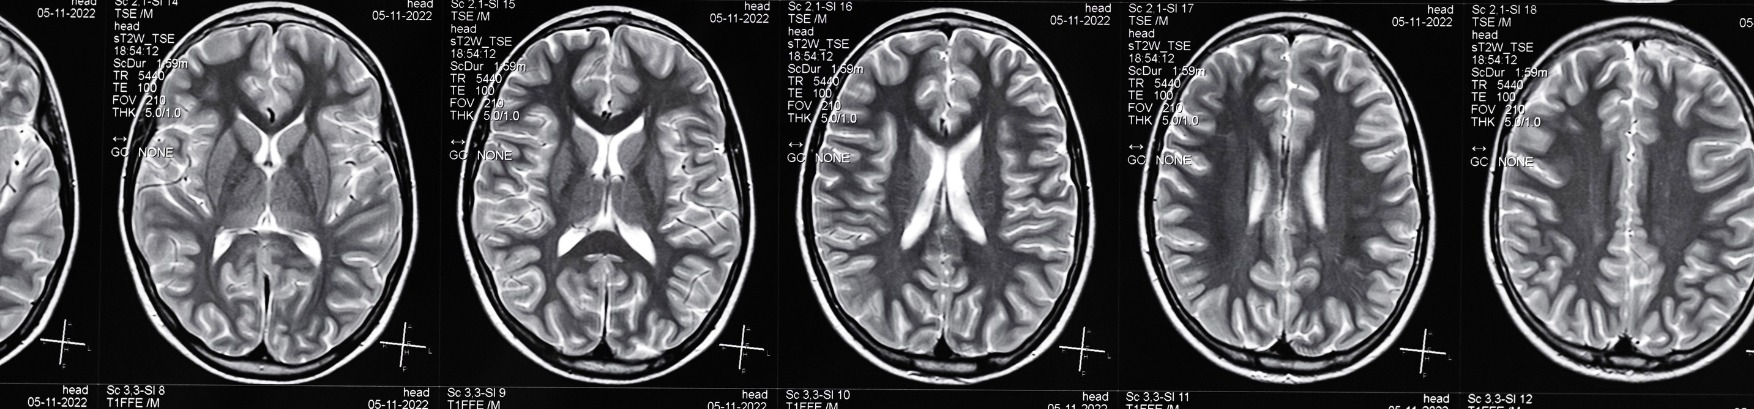

Traumatic Brain Injuries (TBIs) are severe disruptions to normal brain function caused by a sudden blow or jolt to the head or body. They can range from mild concussions to more severe cases resulting in long-term complications. Understanding TBIs, their symptoms, treatment, and the crucial role of a traumatic brain injury lawyer or TBI lawyer is pivotal for individuals navigating such complex and life-altering situations.

Moderate to severe TBIs can have profound and lasting implications. They might lead to cognitive impairments, memory loss, altered sensation, changes in emotional behavior, and sometimes, a coma or persistent vegetative state. The repercussions can affect a person’s ability to work, socialize, and perform routine activities, impacting not just the individual but also their family and support network.

TBIs occur when an external force causes brain dysfunction. This can happen due to various incidents, such as car accidents, sports injuries, falls, assaults, or combat-related injuries. The severity of a TBI can vary widely, from mild cases resulting in temporary symptoms to severe cases leading to permanent impairment or even death.